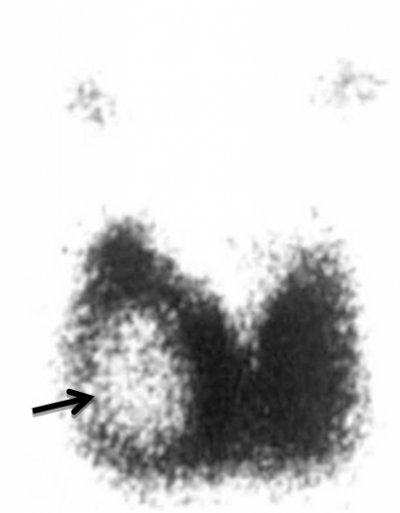

- מיפוי הבלוטה על-ידי חומר מסומן כמו טכנציום פרטכנטט (Tc-99m Pertechnetate) מראה את מבנה הבלוטה ופגמים שבה (תצלום 3.14).

- מיפוי עם יוד מסומן - מלמד על התפקוד של הבלוטה והאם הנגע שבה קולט יוד או לא. קשר קר משמעותו קשר שלא קולט יוד ולכן מחייב בירור לשלילת שאת; קשר חם - קולט יוד ובדרך כלל מלמד על קשר המתפקד עצמאית. קליטה ירודה בכל הבלוטה מלמדת על ירידה בתפקוד עקב דלקת התירואיד או היפותירואידיזם וכו'.

דיקור שאיבה במחלות בלוטת התריס

אחת הבעיות במחלות בלוטת התריס היא, כיצד להבדיל בין קשרית שפירה, ששכיחותה גבוהה, לבין קשרית ממארת, שהיא נדירה, יחסית. קיימות טכניקות קדם-ניתוחיות להשלמת ההערכה הקלינית של קשרית בבלוטת התריס. החשובה שבהן היא סריקה בעזרת חומר רדיואקטיבי, המסווגת את הקשריות ל"חמות" - שהן בעלות פעילות הורמונלית ושיעור ממאירות קטן מאוד, ול"קרות" - שאינן פעילות; מקובלת הדעה, שרוב השאתות הממאירות הן קרות. עם זאת, רוב הקשריות הקרות - שפירות.